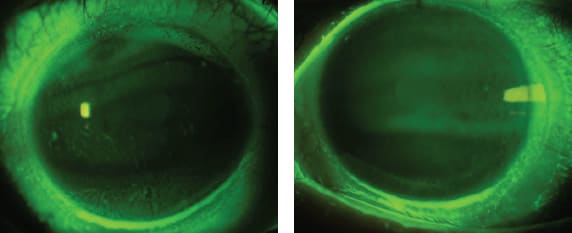

Before applying a lens, we defined the fitting goals as: to improve the overall comfort, to visually rehabilitate the eye, and to protect the eye from further exposure and desiccation. Based on her ocular history, there was no suspicion of any anatomical hurdles to the fitting. Slit lamp examination confirmed these findings. There were dense superficial punctate erosions (Figure 1). The patient had poor vision due to the dense punctate keratopathy and an inability to keep the eye open for prolonged periods of time.

Figure 1. The top image is the initial clinical appearance of Patient #1 showing dense punctate epithelial erosions in the setting of keratoconjunctivitis sicca and lagophthalmos. The bottom image is the same eye after almost five hours of scleral contact lens wear. Note the smooth corneal surface and absence of staining.

The patient demonstrated dramatic immediate relief upon application of the first diagnostic device. The exiting visual acuity was 20/25 OS with an 18.5mm spherical scleral lens design. The total sagittal depth was 555µm. Wearing the scleral lens dramatically decreased the patient's corneal staining (Figure 1, bottom). Scleral lens wear supports resurfacing of the ocular surface in a relatively quick period of time. In our experience, the corneal staining will reappear after not wearing the device.